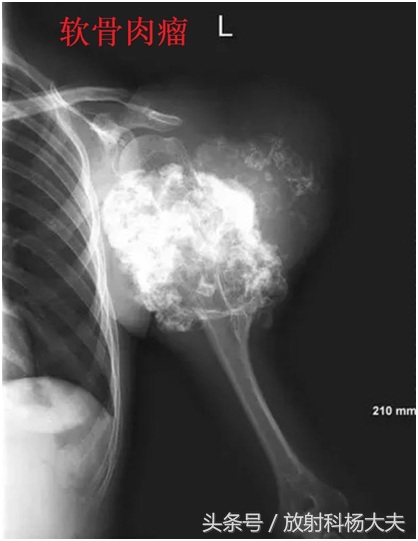

比如,下面的图,都是恶性的。

在骨关节的X线片上,通常在骨骼或骨骼边上看到这种高密度的类似骨骼一样东西,我们会斟酌哪些?骨肉瘤,软骨肉瘤,创伤性骨炎,还有某些疾病引起的钙化,骨化等等。